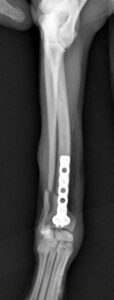

左前腕骨折のトイプードルちゃんの手術がありました。橈尺骨骨折は動物病院では一番よくある骨折です。ロッキングプレートであるTAITANコンディラー1.7mmで対応しました。治りも順調で元気に帰りました。よかったね。